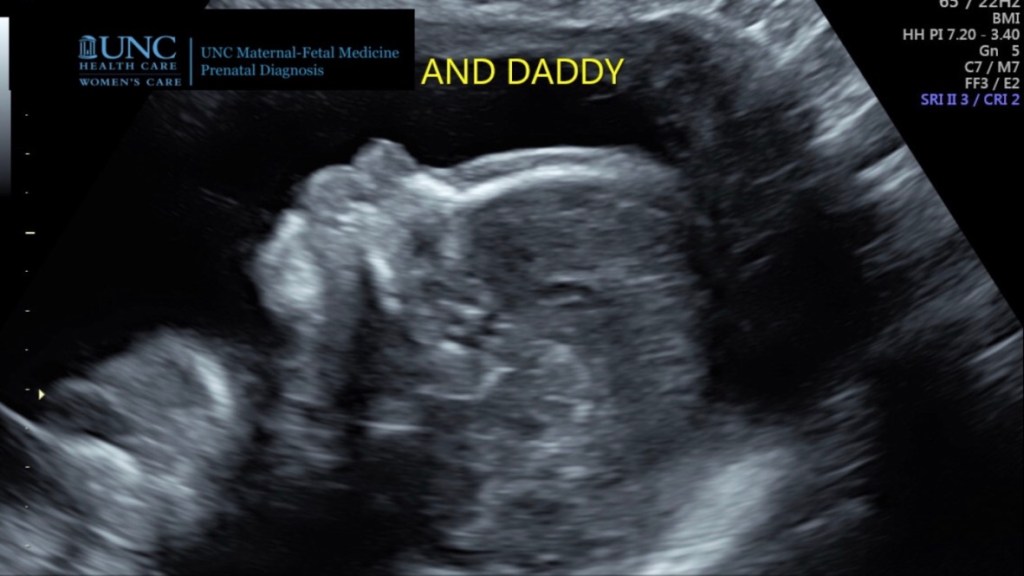

These were the scriptures I had in my heart when Daniel and I were begging for Ginny’s life. In that dark ultrasound room, the technician said that she was having trouble finding the heartbeat. I started panicking. Then I remembered that my God works miracles. The technician left to get a doctor, and Daniel and I prayed harder than we’ve ever prayed before. In Jesus Name Ginny Will Be Born Alive!! We are asking for a MIRACLE! Please please let Ginny grow up. Give her life! Please FATHER!!

The doctor arrived, “I’m so sorry.” We had our answer. I was shocked.